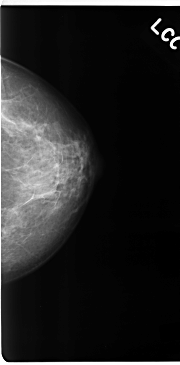

C_0115_1.LEFT_CC

LEFT_CC LINES 4744 PIXELS_PER_LINE 2328 BITS_PER_PIXEL 12 RESOLUTION 50 NON_OVERLAY